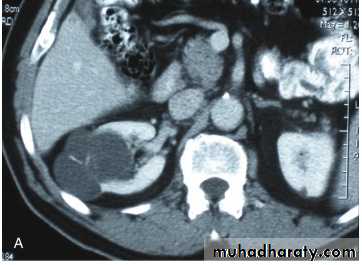

Ct enhanced

Renal cyst type 4 with calcification and peripheral enhancement needs radical nephrectomyBosniak's class II renal cysts. A, CT scan shows right renal cyst with thin internal septation.